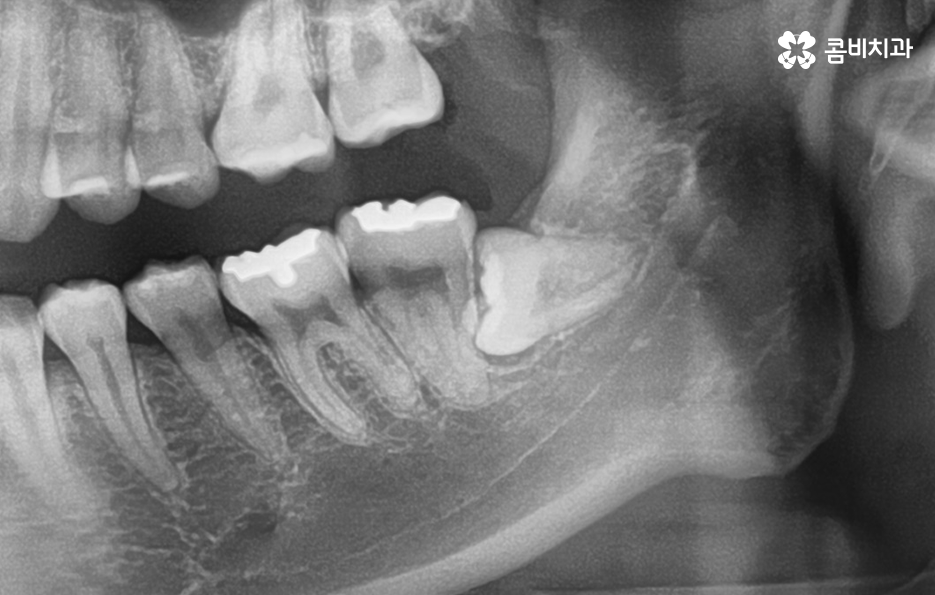

정상적으로 맹출된 사랑니가 아닌 사진에서 보시는 사랑니의 케이스처럼 어금니 부분으로 완전히 누워있는 사랑니의 경우에는 늦지 않게 발치 계획을 세우시길 권하고 있습니다

사랑니 발치에 대해 시점이 중요한 이유 중에 하나는 어금니와 인접하기 때문에 정상적인 위치와 방향으로 맹출된 사랑니라도 청결관리 문제로 인해 어금니에도 악영향을 주는 사례가 많기 때문인데 누워있는 사랑니의 경우에는 청결관리와 무관하게 어금니 손상을 일으키는 경우가 많기 때문에 미리 예방적으로 발치를 권하는 경우가 많이 있어요

누운 사랑니 발치를 미리 예방적으로 하면 좋은 이유는 어금니 방향으로 누워서 자라는 사랑니는 아무리 청결관리를 잘해도 보통 3,40대 이후에는 어금니를 썩게 만들고 어금니 충치가 심해져서 심한 경우 어금니 마저 발치하게 되는 경우가 많이 있는데요

사랑니 하면 어떤 사랑니든지 언젠가는 문제가 될 수 있겠지만 그중에서도 위 사진에서 보여지는 누운 사랑니의 정도라면 그 시점이 3,40대 전후에도 문제가 커질 수 있다는 점에서 최소한 경각심을 갖고 문제가 커질 수 있음을 먼저 인지하시고 대학병원 혹은 사랑니를 전문적으로 발치할 수 있는 치과에서 치료 계획을 세우시길 권하고 있어요

위 사례 이미지의 경우 그래도 다행인 점은 사랑니 발치 시점이 늦지 않아서 완전 누운 사랑니 임에도 큰 고생은 안했던 사례라고 본다면 아래 환자분의 사례는 이미 사랑니 뿐 아니라 어금니 까지 충치가 심해진 사례라고 할 수 있는데요